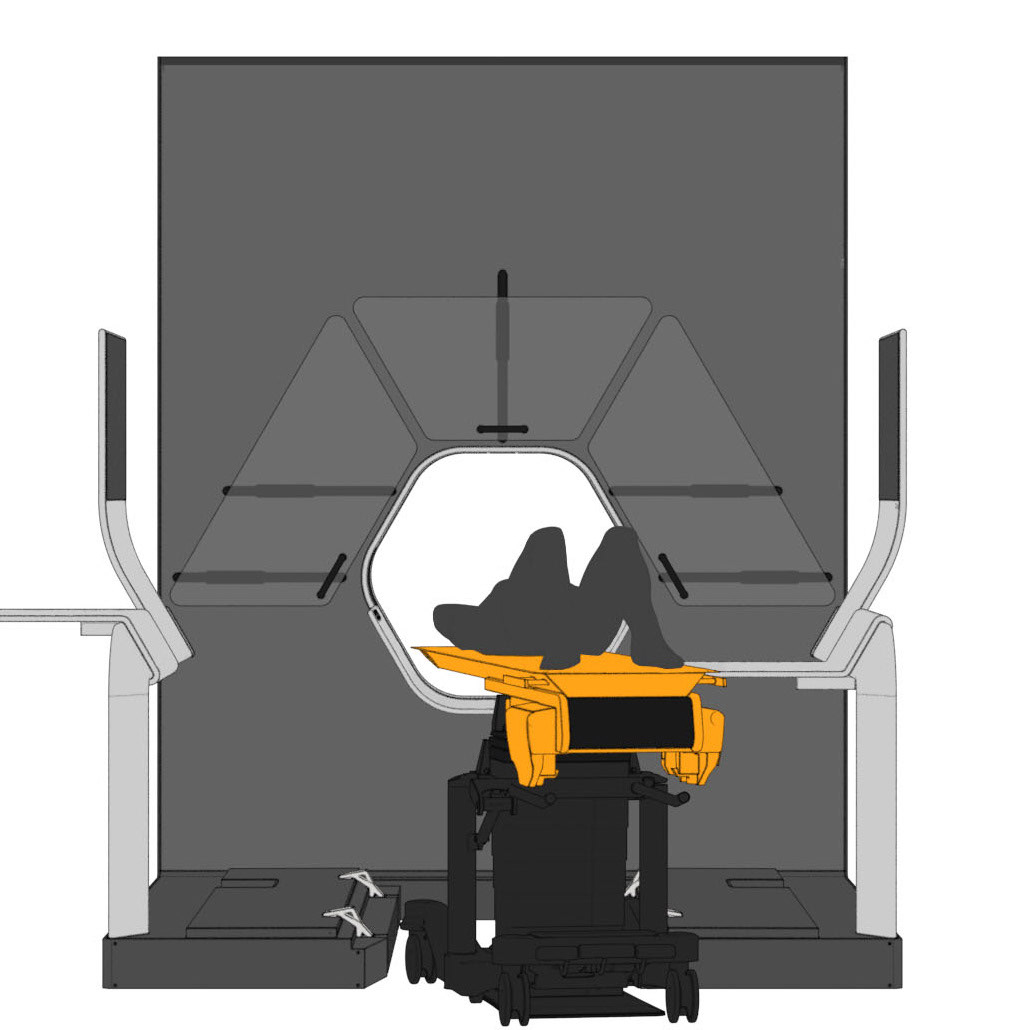

The central design feature is the hexagonal gantry opening. It provides space for the lamps and displays. The large fronts of the gantry offer space for a display of different coloured patterns and animations, which visualize the radiation. These can be individually selected and adapted together with the overall height of the gantry. The patterns pick up on the hexagonal shape of the gantry opening and set it off. To protect the interventionists from radiation, lead glass panels and a radiation protection tray are installed. The sliding lead glass panels allow individual adaptation to the patient and the interventionists working space. The tray serves to protect the abdomen and offers a lot of foot space as well as a front leaning aid for a safe stand.

Due to the new position and height of the gantry opening, the isocenter is shifted upward compared to conventional CT units. In order for the physician to operate as usual in the isocenter, his platform must also be shifted upward by this height difference. A review in VR showed that a platform height of 15cm provides the optimal comfort for the interventionalist.

The patient bench can compensate for the height difference of the isocenter by its height adjustability. Even in transport mode, the patient bench can be inserted into the opening without collision. Thus, no elevation is necessary for the couch.

Various tables can be suspended on the railing. This enables the individual positioning of surgical instruments and devices. To relieve the interventionists, it is also possible to lean against the railing, similar to a standing seat in a gondola or tram. In addition, the railing offers protection against a potential fall from the platform.